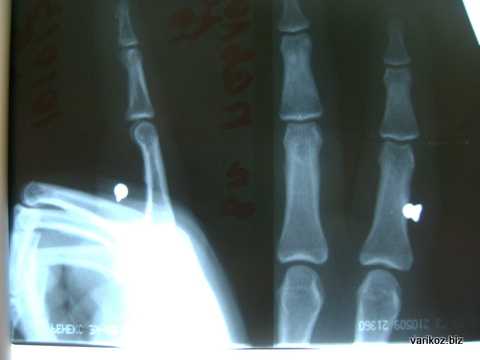

На фото - инородное тело - пуля от пневматической винтовки в пальце кисти.

По свидетельствам специалистов ИТ чаще всего локализуются в пястье, пальцах, реже - в запястье руки. При огнестрельных ранах ИТ рассеиваются по всей площади кисти.

Заподозрить присутствие ИТ возможно с помощью визуального осмотра и пальпации. В особых случаях назначается рентгенодиагностика, которая включает рентгенографию, рентгеноскопию, электрорентгенографию. Все ИТ классифицируются как рентген контрастные - видимые на снимке при рентгенографии, малоконтрастные - трудно определяемые на рентгеновском снимке, и рентген неконтрастные - не проявляющиеся при рентгенографии. Последние могут быть выявлены с помощью ультразвукового исследования.

Инородные тела чаще задерживаются в пясти — 47 %, затем в пальцах — 36,8%, реже в запястье — 10,1 %. Изредка, главным образом при огнестрельных ранениях, они бывают рассеяны по всей кисти — 2,5%, и в 3,6% локализация не уточнена. Большинство хирургов считают, что не все инородные тела сразу подлежат удалению. Исключение составляют лишь графит, кусочки краски, подлежащие удалению из-за опасности вызываемого ими некроза тканей.